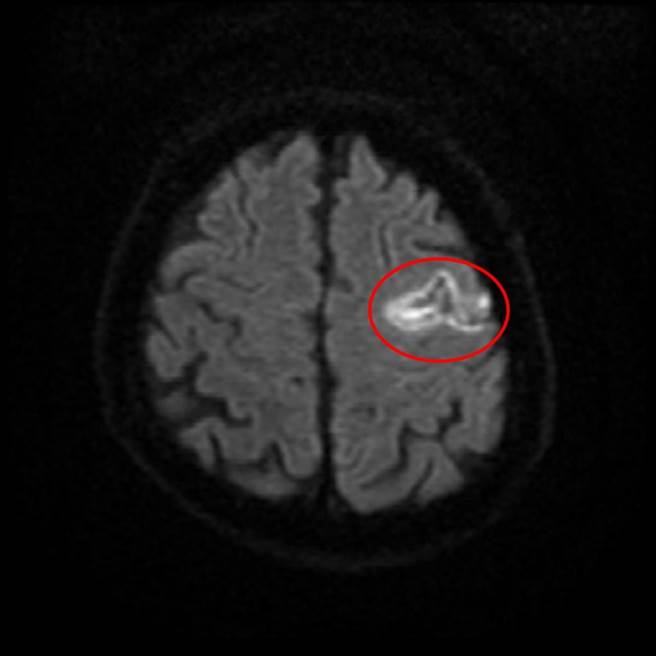

有糖尿病、心房颤动病史的65岁王姓男子,日前凌晨醒来时感觉左半身无力、讲话变得模糊不清等疑似中风症状,就医检查发现脑部大血管未阻塞,研判为缺血性脑中风,紧急施打「血栓溶解剂」后,恢復良好;医师强调,心房颤动是导致缺血性中风的危险因子之一,患者应留意。

王男经施打血栓溶解剂,后续虽仍有部分脑出血情况,但仅造成他有些微说话不流畅、较原本说话像含着滷蛋的情况好许多,其余功能都恢復良好。医院表示,王男就医期间会诊心臟内科医师、寻找病因,经抽丝剥茧,确认其致病原因与心房颤动有关。

邱新藻说,「缺血性脑中风」在台湾中风型态中约占8成,可能因心臟血栓流到脑部或血管硬化导致,通常与三高、老化等情况有关,若未及时注射溶解剂恐引发脑部损伤;此外,心臟跳动不规则就易产生血栓,若血栓跑到脑部就会造成脑中风,因此,心房颤动也是引发此病症的危险因子。